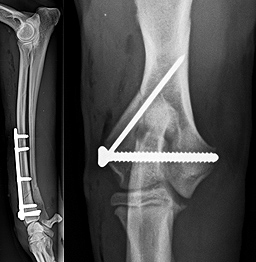

Mein Forschungsinteresse liegt in der Orthopädie. Bereits während meines chirurgischen Spezialistentrainings an der Universität Lüttich habe ich begonnen, mich mit den komplexen Anforderungen der Knochenheilung auseinander zu setzen. Die optimale Frakturheilung hängt von verschiedenen Faktoren ab, wie z.B. Weichteiltrauma, Art und Lokalisierung der Fraktur, Alter des Tieres etc. Dadurch ist jeder Knochenbruch sehr individuell und eine standardisierte Frakturversorgung ist nicht möglich oder ratsam. Stets gilt es, eine Balance zwischen ausreichender Stabilität und erforderlicher Elastizität zu schaffen und gleichzeitig die Anzahl und Art der Implantate anzupassen. |

Wie Frakturen entstehen, wie die Stressverteilung im Knochen vor Auftreten der Fraktur und nach Osteosynthese verläuft, und welche Implantate bei den jeweiligen Frakturtypen verwendet werden sollten, ist derzeit unser Forschungsschwerpunkt. Die Auswahl der Implantate basiert derzeit oft auf Erfahrungswerten und mechanischen Tests, ist aber in vielen Fällen klinisch noch nicht wissenschaftlich validiert. Mit unserem Forschungsprojekt soll diese Validierung anhand von Computersimulationen ermöglicht werden. Zu diesem Zweck werden verschiedenen Frakturtypen und Frakturlokalisationen an einem Computermodell nachgebildet und die klassischen Implantate simuliert. Bereiche verstärkter Beanspruchung werden sichtbar gemacht und Verbesserungsvorschläge können am Computer getestet werden. Langfristig soll eine Computersoftware erarbeitet werden, die den Kleintierchirurgen eine Entscheidungshilfe an die Hand gibt.